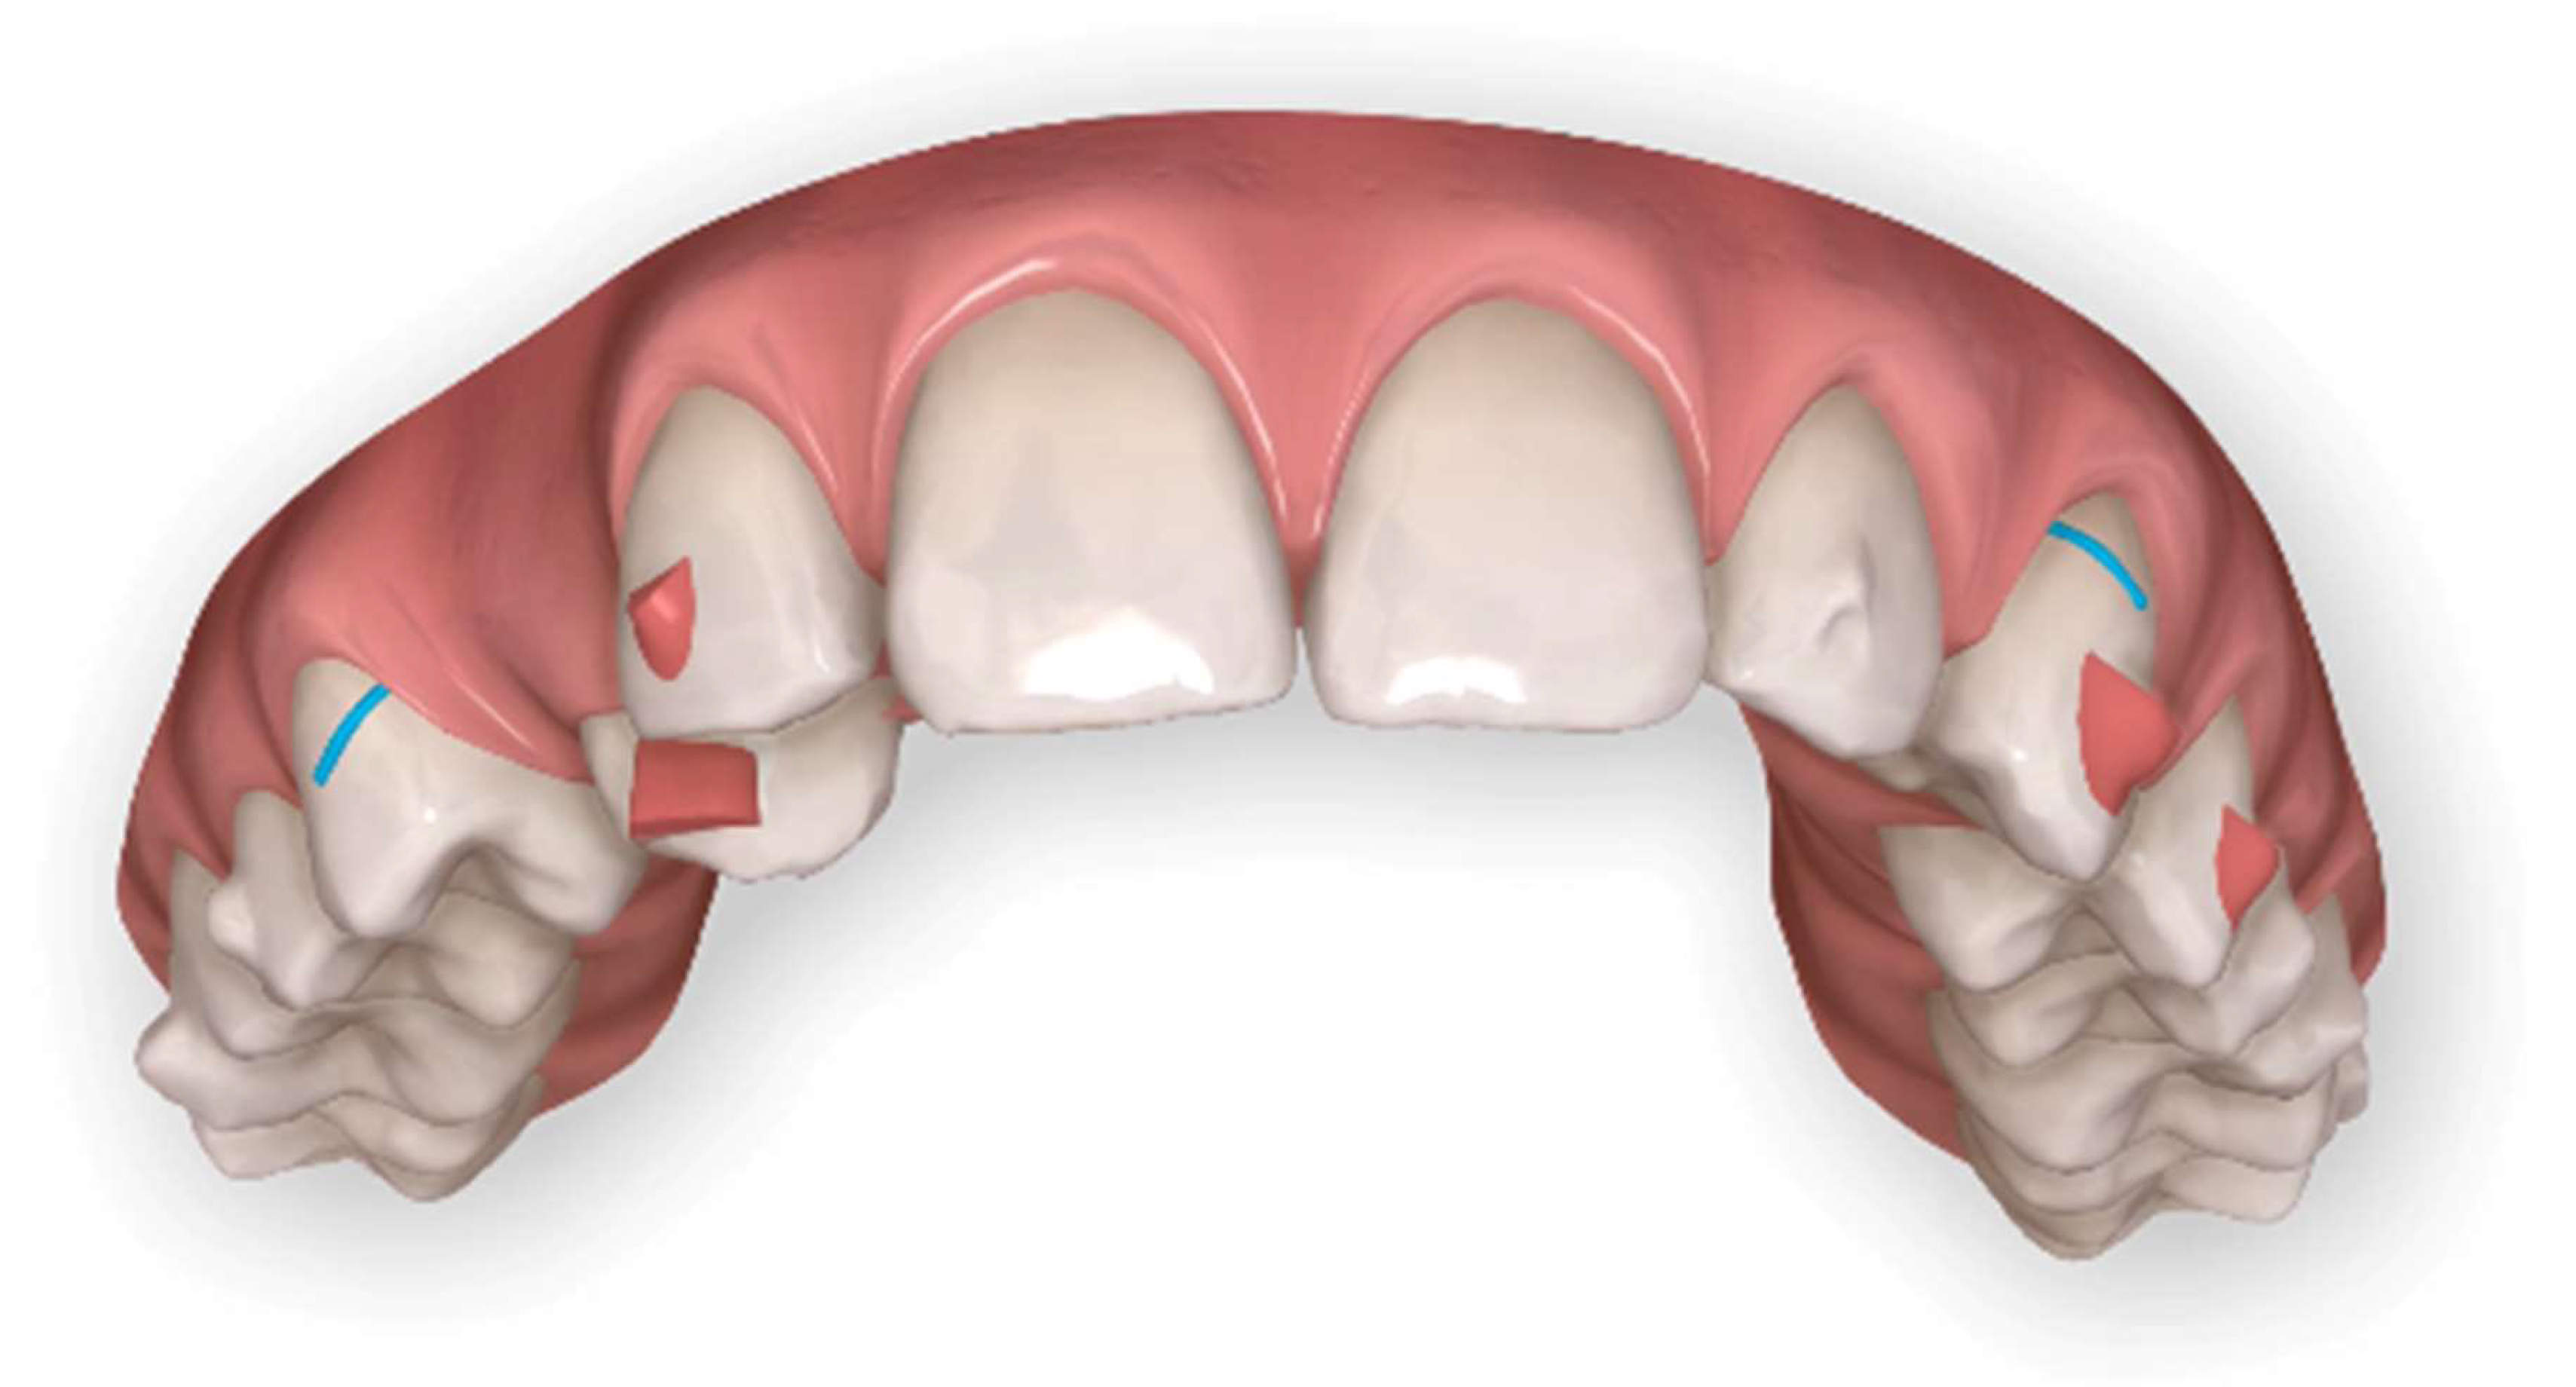

A horizontal rectangular attachment was placed on the buccal surface of the canine and a buccal root torque was applied to ensure the three-dimensional control of the tooth movement (Figure 8).

Figure 8.

Horizontal Rectangular gingival bevelled attachment to improve the fitting on the 1.3 and buccal root torque.

A horizontal rectangular attachment was placed on the buccal surface of the canine, and lingual root torque was applied to ensure the three-dimensional control of the tooth movement (Figure 16).

Figure 16.

Digital impressions after the first set of aligners and a new Clincheck® to refine the occlusion.